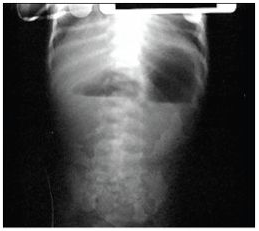

A premature infant is born by normal vaginal delivery without complication. There is no respiratory distress. Upon the first feed, she begins vomiting gastric and bilious material. CXR is shown. What is the most likely diagnosis?

Duodenal atresia. Half of infants with this condition are born prematurely, and the condition is associated with Down syndrome. Look for polyhydramnios in the prenatal exam. Treatment involves NG decompression and surgical correction. You must search for other abnormalities (VACTERL association) with X-ray of the spine, abdominal ultrasound, and echocardiogram

List the differential diagnosis of double-bubble seen on abdominal X-ray of newborn infants